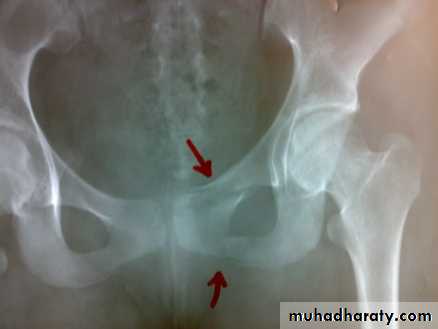

Unstable ring fractures

There are fractures around or separation of symphysis pubis or sacroiliac joint.

Types of unstable fracture pelvic ring

1- antero-posterior compression (open book).

2- lateral compression (closed book).

3- Vertical force cause vertical displacement of the innominate bone on the same side.

4- combination injuries.